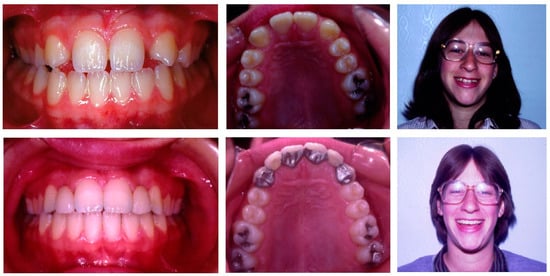

- To demonstrate the clinical management of agenesis of maxillary lateral incisors specifically, because of esthetic concerns, and that of missing second premolars.